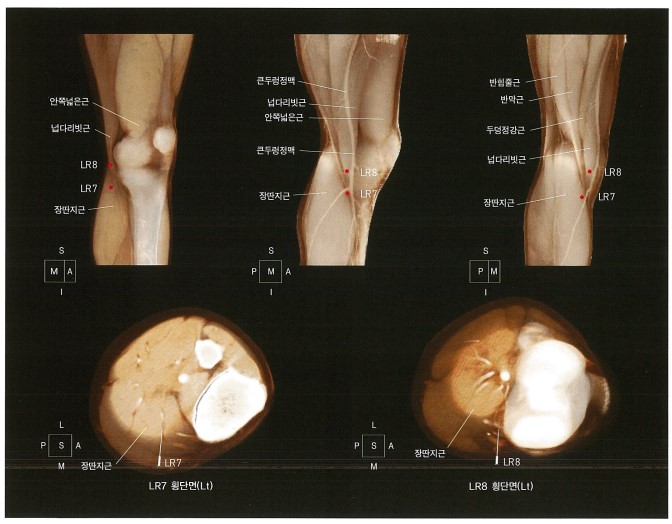

족궐음간경 "곡천(曲泉)혈"(LR 8)은 무릎 안쪽면, 오금주름(popliteal crease)의 안쪽 끝, 반막양근의 안쪽 오목한 곳에 해당됩니다.** 경혈학 교과서에 기술에 따르면, 곡천혈은 서근활락(舒筋活絡)의 효능이 있어 한습풍비(寒濕風痺), 근련(筋攣), 슬통(膝痛) 등을 치료한다고 되어있습니다.**

즉, 근육을 이완시키고 무릎 관절낭염을 치료하는 혈자리**라고 볼 수 있겠네요. 해부학적인 위치 뿐만 아니라, 혈자리의 효능으로 보아 베이커 낭종 및 무릎 관절염을 치료하는 특효혈이 되겠습니다.